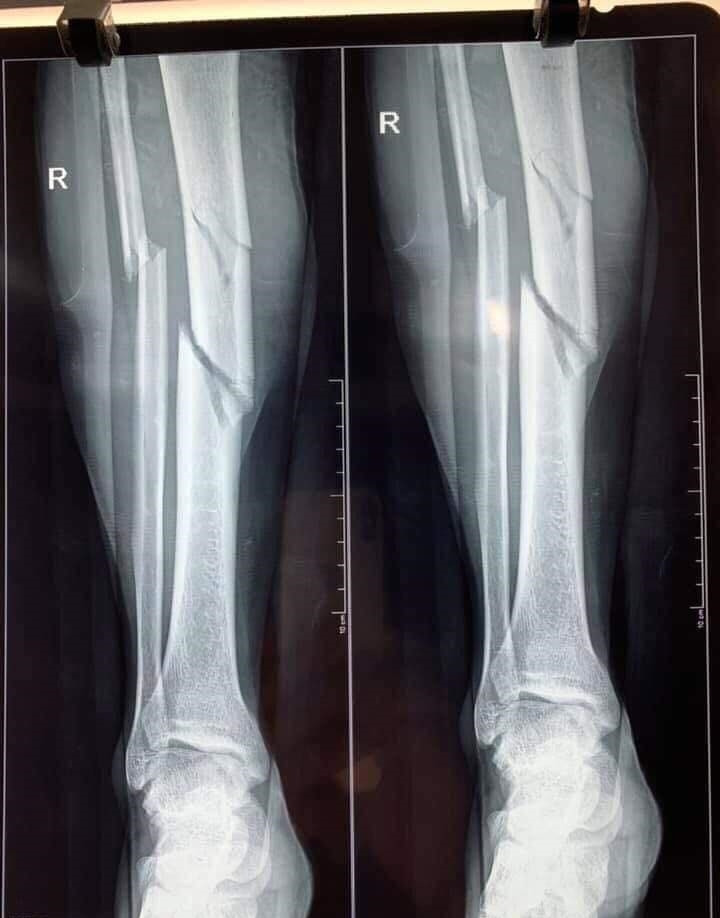

Theo đó, sau cú va chạm mạnh, một cầu thủ bị thương khá nặng và phải đưa đi cấp cứu ở bệnh viện. Kết quả chụp X-quang cho thấy, phần xương ở bắp chân đã bị gãy làm ba và phải tiến hành phẫu thuật gấp. Ngay sau đó, người thân, bạn bè của cầu thủ này đã kêu gọi hỗ trợ để giúp anh có đủ kinh phí tiến hành cứu chữa. Thật may mắn, ca phẫu thuật đã thành công.

| Một va chạm trên sân bóng đã khiến phần xương bị gãy làm ba. (Ảnh: T.D.) |